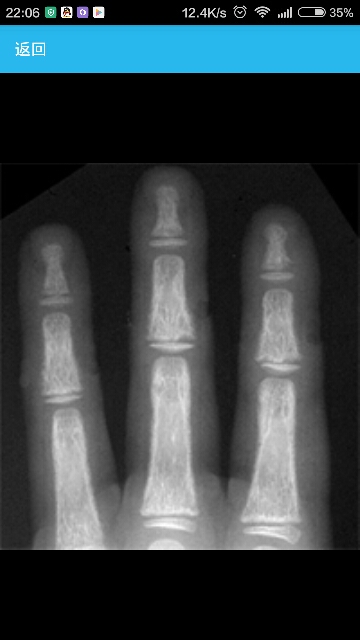

男性,45岁,四肢长骨及关节明显触痛。 病史临床诊断为梗阻性肾病、慢性肾衰竭行维持性血液透析8年。每周透析3次,每次4小时,干体重65公斤,使用1.7m2聚砜膜高通量血液透析器治疗,透析剂量评估Kt/V=1.4。 辅助检查血清总钙2.6 mmol/L,血清磷2.2 mmol/L,血清全段甲状旁腺激素820 pg/mL,碱性磷酸酶350 U/L,肝功能正常,血清白蛋白41 g/L。X线检查提示符合纤维性骨炎改变并软组织钙化。超声心动图检查提示心脏瓣膜钙化和颈动脉钙化斑块。B超检查未发现增大甲状旁腺。 诊断慢性肾衰竭(CKD 5期)并继发性甲状旁腺功能亢进,肾性骨病。 治疗①首先必须控制高磷血症,以避免钙磷乘积过高导致难于逆转的转移性钙化;   ②磷结合剂氢氧化铝凝胶一般不宜使用,以免引起铝的贮积。高磷血症控制后,维持治疗期间以使用碳酸钙为宜;如钙磷乘积不高,应首先选用碳酸钙;   ③要定期观察血钙,以免血钙过高造成的损害,当血钙大于2.75 mol/L时应及时停药;   ④适当降低透析液中钙的浓度:如透析液中钙离子浓度小于1.25-1.75 mol/l(5~7 mg/dl),可显著减少高钙血症的发生率; ⑤对于未曾使用1,25(OH)2D3的病人,首先选择小剂量治疗。如果效果欠佳或病人出现难于纠正的高甲状旁腺激素血症,可考虑使用静脉或口服1,25(OH)2D3冲击治疗方案。